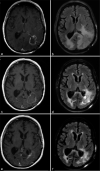

Background: Laser interstitial thermal therapy (LITT) is a minimally invasive surgical treatment for multiple intracranial pathologies that are of growing interest to neurosurgeons and their patients and is emerging as an effective alternative to standard of care open surgery in the neurosurgical armamentarium. This option was initially considered for those patients with medical comorbidities and lesion-specific characteristics that confer excessively high risk for resection through a standard craniotomy approach but indications are changing.

Results: This review provides an update of the relevant literature regarding application of LITT in neurosurgical oncology for the treatment of de novo and recurrent primary gliomas and brain metastases radiographically regrowing after previous irradiation as recurrent tumor or RN. In addition, this review details the limited experience of LITT with meningiomas and symptomatic peritumoral edema after radiosurgery. The advantages and disadvantages, indications, and comparisons to standard of care treatments such as craniotomy for open surgical resection are discussed for each pathology. Finally, the literature on cost-benefit analyses for LITT are reviewed.